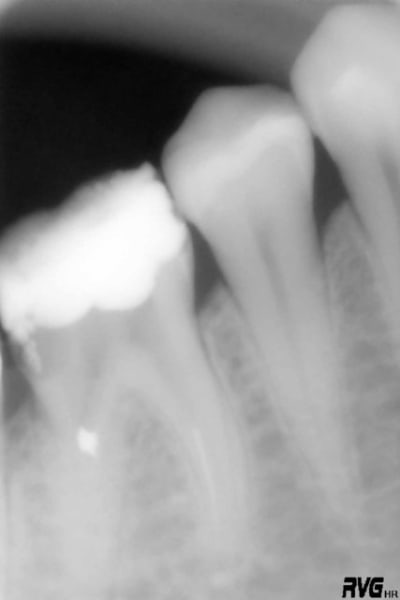

Je commence avec ce bout de F2 que j'ai ostéointégré :( à l'extrémité de la racine Distovestibulaire de cette 17. A l'origine, un "buggage" du localisateur d'apex. Je ferai dorénévement tout de meme une petite rvg de controle....